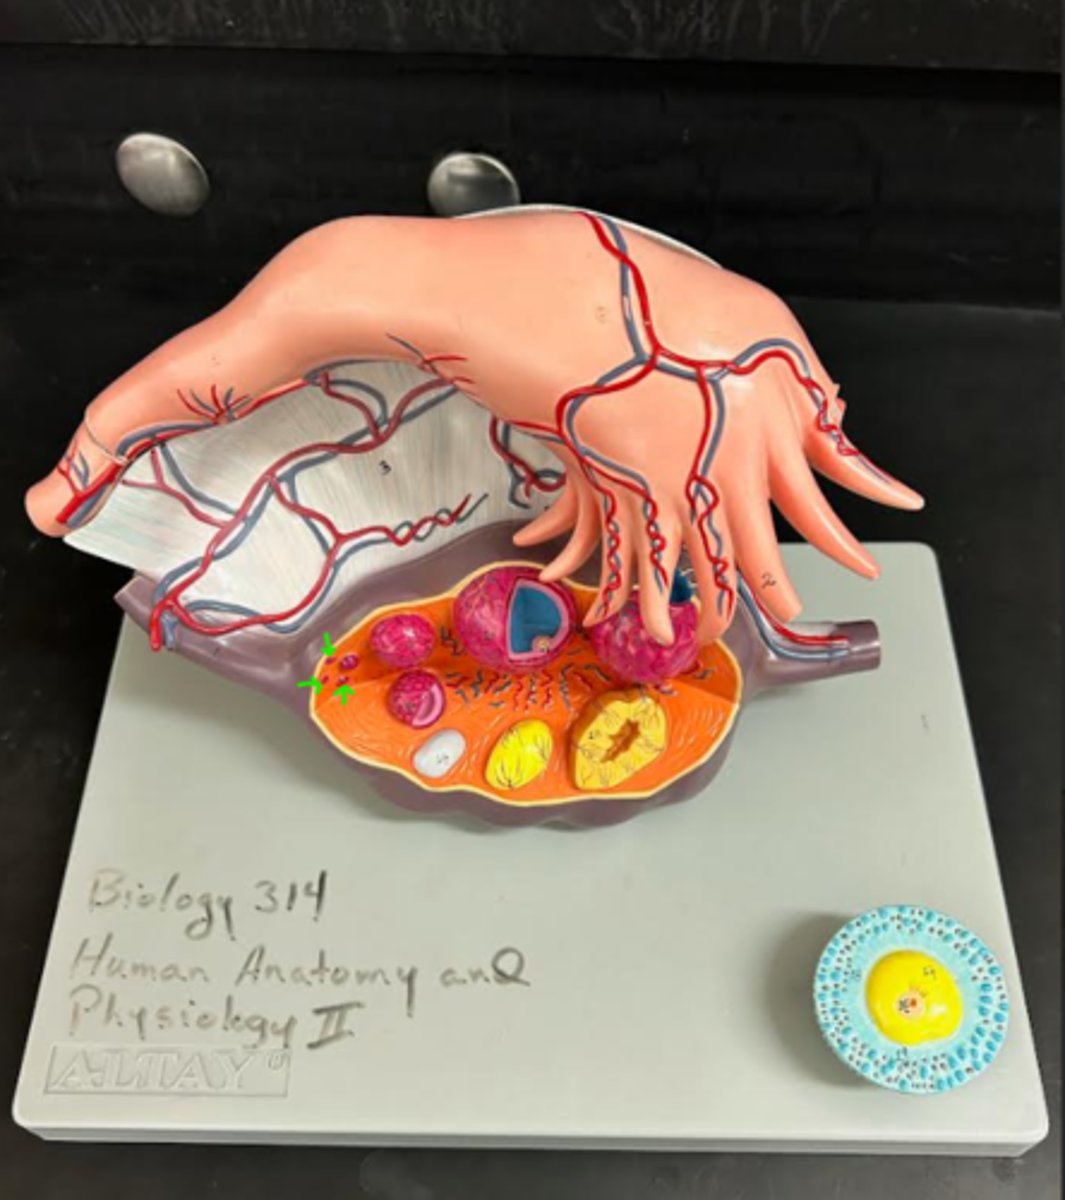

ovary

1

primordial follicle

a

secondary follicle

b

ruptured follicle

c

granulosa cells

d

corpus luteum

e

secondary oocyte

g

ovum

h

zygote

i

blastocyst

l

endometrium

m

corpus albicans

f

uterus

3

fallopian tube

2

right ovary

1 (lt or rt)

infundibulum

2

ampulla

3

isthmus

4

fundus

5